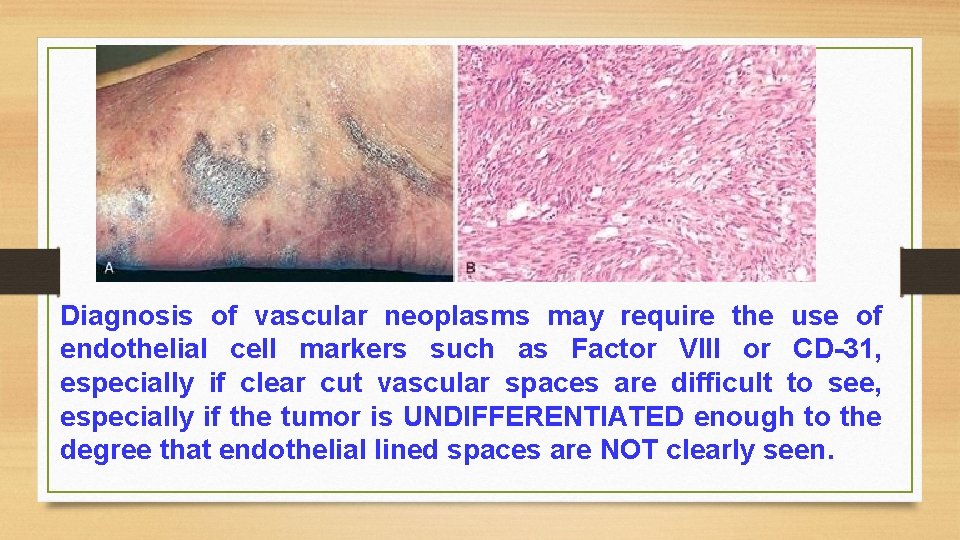

A. Benign Tumors (never metastasize): 1. Haemangioma (see general). 2. Lymphangioma. 3. Glomus tumor (glomangioma). B. Intermediate Grade Tumors (rarely metastasize but recurrence is common): 1. Haemangioendothelioma. 2. Kaposi's sarcoma. C. Malignant Tumors (frequent and early metastasis): 1. Angiosarcoma. 2. Lymphangiosarcoma. N. B. Diagnosis of vascular neoplasms may require the use of endothelial cell markers such as Factor VIII or CD-31, especially if clear cut vascular spaces are difficult to see , especially if the tumor is undifferentiated enough to the degree that endothelial lined spaces are not clearly seen.

Diagnosis of vascular neoplasms may require the use of endothelial cell markers such as Factor VIII or CD-31, especially if clear cut vascular spaces are difficult to see, especially if the tumor is UNDIFFERENTIATED enough to the degree that endothelial lined spaces are NOT clearly seen.